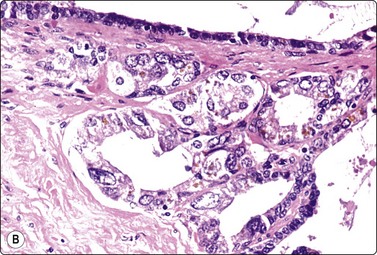

image

Fig. 13.9 Basal cell (atypical) hyperplasia

Sheets of glandular epithelial cells showing mild nuclear enlargement and nuclear crowding contrasting with normal epithelium (A, DQ; B, Pap, HP).

Fig. 13.10 Basal cell hyperplasia

Corresponding tissue section (H&E, IP).

PIN should not be diagnosed by tFNA alone.28 We use the term ‘atypical cells’ when the atypia and cellularity are below the requirements needed to reach a confident diagnosis of malignancy, and submit the patient for systematic TNCB. Histology of these cases almost always reveals either high-grade PIN or low-grade carcinoma. Pathologists should refrain from making a definitive diagnosis of malignancy when the smears contain only a small proportion of cells with malignant features.